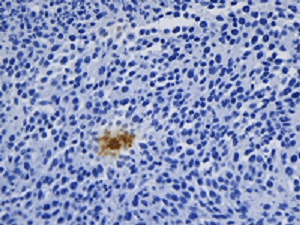

2. ÃâŌßŊMģ¯Ŗ¨IHCŖŠŖēŊâ´aÄ[ÁöˇÖ×ĶĖØÕ÷

ͨß^Ã÷ÃĀML51-NÉúÎīī@ÎĸįRÅcMSX2ĪāCĩÄŊMēĪŖŦŋɲļĢ@¸ßŲ|ÁŋĩÄÃâŌßŊMģ¯DĪņŖ¨ČįHER2ĩ°°×ąíß_zyŖŠŖŦÖąĶ^ÕšĘžÄ[ÁöˇÖ×ĶˇÖĐÍÅcŅĒšÜÉúŗÉĮérŖŦéÖίˇŊ°¸ÖÆļ¨ēÍîAēķÔušĀĖᚊęPæIĐÅĪĸĄŖ